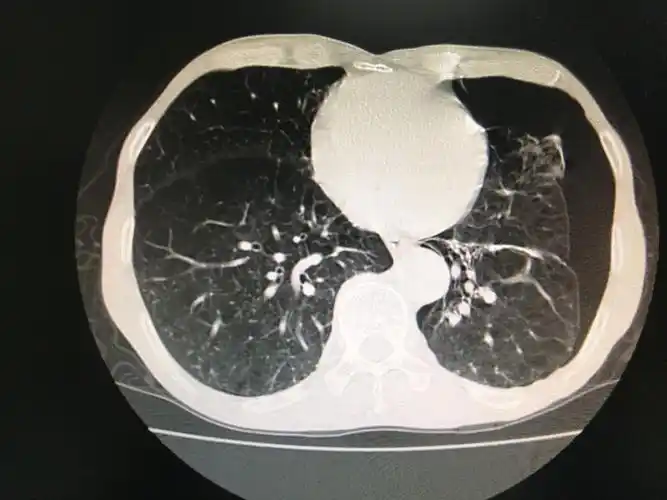

多发巨大肺大疱并自发性气胸病人1例

ct片示徐大叔多发肺大泡形成

左肺巨大肺大泡一例

双肺肺气肿伴右肺巨大肺大泡.